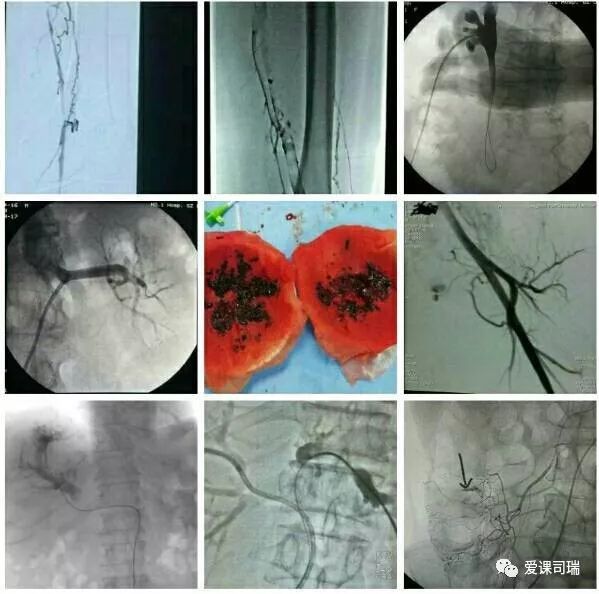

总的说来,如果吃药效果不佳,又不能或不愿开刀的病,都可能通过介入方法得到解决。比如动脉、静脉、尿路、胆道等处堵塞,咯血、便血、尿血、呕血,糖尿病下肢冰凉,甚至是顽固性高血压等等,介入医生用针和细小的导管等器材,无须开刀,也许就能顺利解决,见效往往还很快。如果有这些情况,不妨找介入医生看看。

概括地说,介入诊疗有以下优势: 1.可以远道施术:借助于导管等器材,可以从对病人最有利、远离病变的部位入手,将治疗器材送达病变局部,再施行精细的治疗。比如,头部有病,我们可以方便地从大腿跟部进管,经血管插管到头部去,从而避免直接切割或穿刺头部。 2.创伤轻微,容易耐受:借助于影像设备这“第三只眼睛”的引导,无须开刀即能清晰显示病变部位,从而进行准确的治疗操作。 3.可重复性强:由于创伤小,不会造成局部的粘连和组织缺损,因而可以多次反复地进行治疗,直到病变完全康复为止。 4.定位准确:有影像设备作实时的引导和监控,没有视觉盲区,因而可以“指哪打哪”。 5.疗效高、见效快:对很多病变可以起到“立竿见影”的效果。 6.并发症发生率低:也就是说安全性高,由上述多种优势的综合作用所致。 7.方便联合应用多种介入技术:介入诊疗技术种类繁多,各有特色和优势,可以方便地联合应用,取长补短,从而进一步增强治疗效果。

“介入”的应用范围涵盖了头颈、胸腹、四肢等各个部位,涉及神经、心血管、呼吸、消化、泌尿生殖、骨关节等各个系统器官的病变诊治。

介入放射学按诊治目的可分为介入诊断学和介入治疗学,按涉及学科可分为神经介入、心血管介入、肿瘤介入、妇产科介入等学科分支;介入诊疗技术按进入途径则可分为血管性和非血管性两大类介入技术。

在影像设备引导下实施操作是介入诊疗的鲜明特色,故影像设备不可或缺。目前最常用的介入引导设备是DSA机(见下图)。B超、CT、MRI也可引导介入,在定位穿刺、肿瘤消融等方面也各具优势。